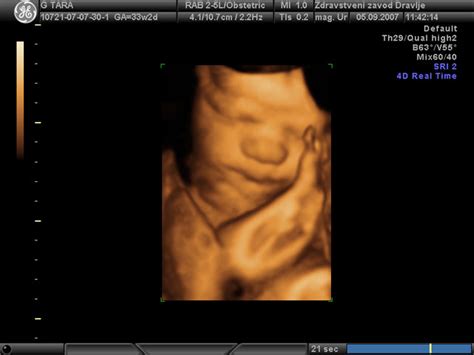

Nosečnica, ki ji grozi prezgodnji porod, se lahko toži o bolečinah v trebuhu ali križu, tiščanju navzdol, povečanem izcedku ali krvavitvi. S fizikalnim pregledom in dodatnimi testi lahko zdravnik ugotovi morebitno odtekanje plodovnice in mesto krvavitve. Ultrazvok se uporablja za preverjanje stanja in rasti ploda, lege posteljice ter morebitnega retroplacentalnega hematoma. Lahko se tudi slučajno ugotovi odprto maternično ustje.